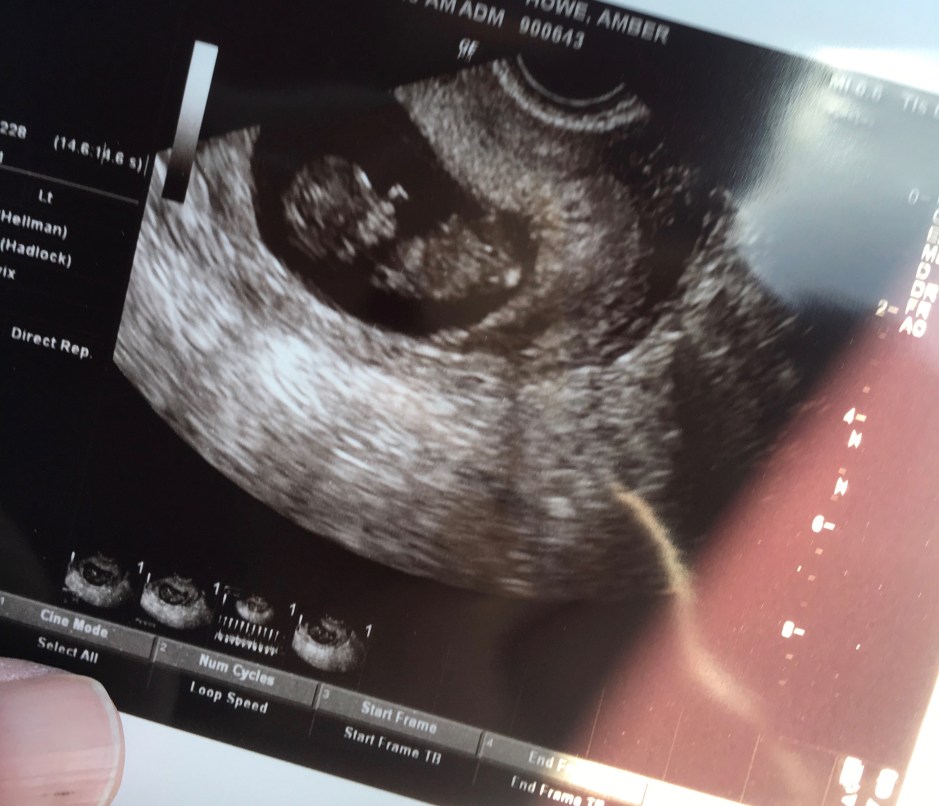

The doctor confirmed our incredible news and we saw our little caboose wiggling around immediately. The best part about working through a fertility clinic is that there are multiple early ultrasounds- lots of chances to see our second rainbow baby and get the reassurance that this is REAL. Look at the thumb-sucking going on already!